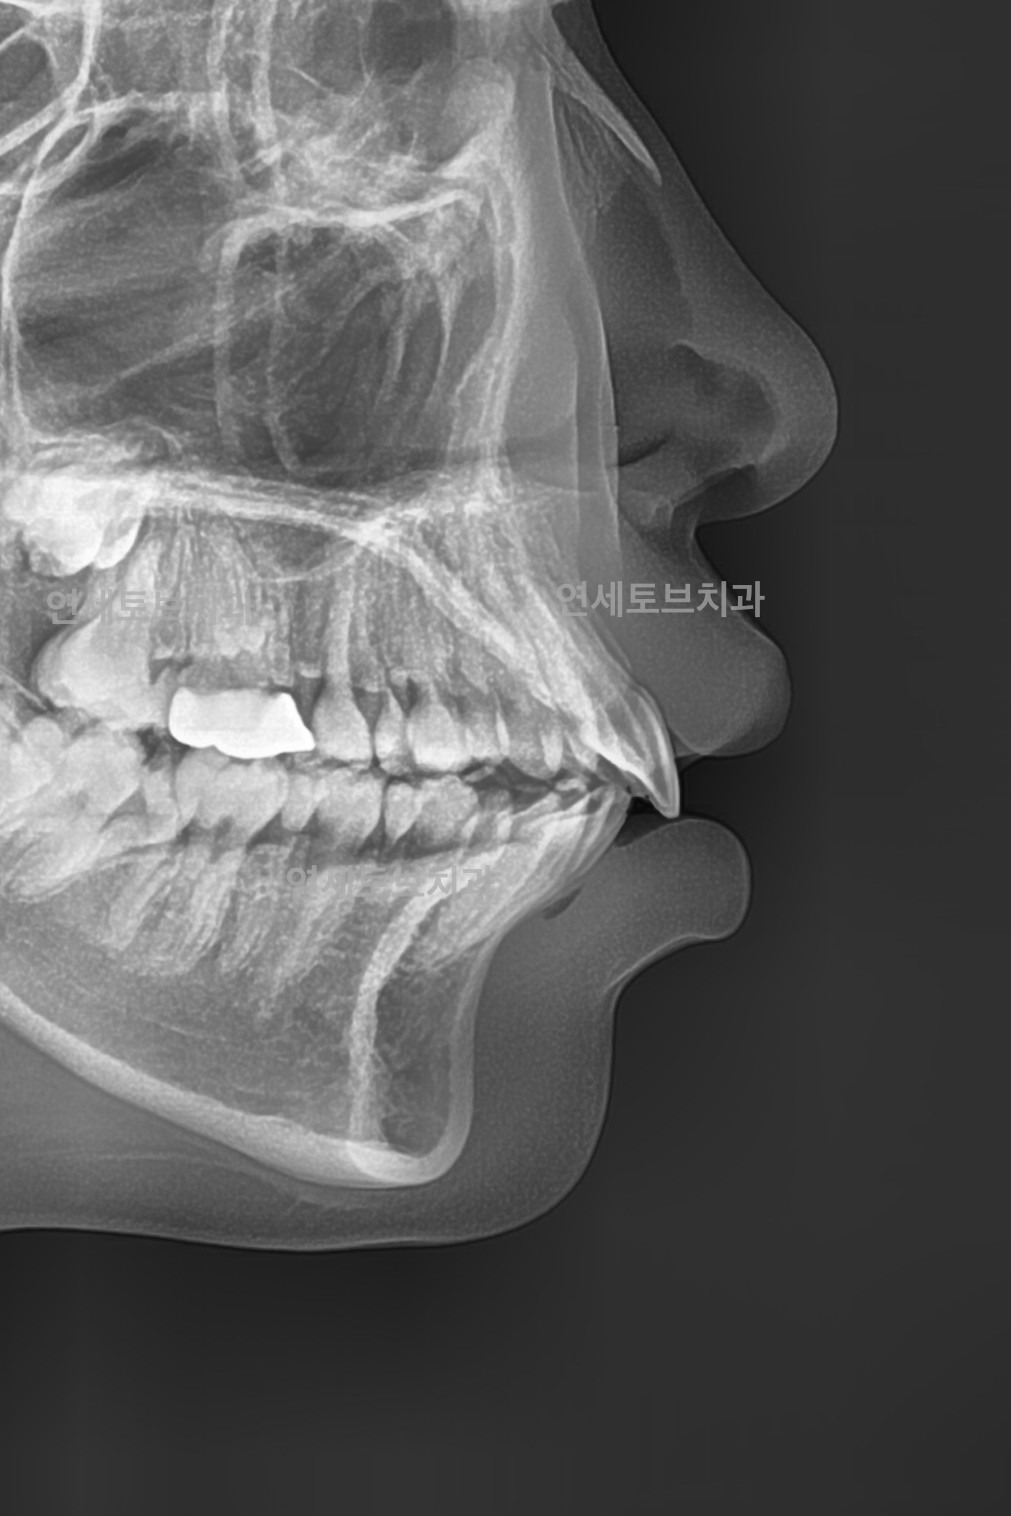

돌출입은 윗니나 아랫니(또는 둘 다)가 정상적인 위치보다 앞으로 튀어나온 상태를 말합니다.

이로 인해 입술이 앞으로 돌출되어 보이고, 측면 얼굴 프로필에서 특히 두드러지게 나타납니다.

Before